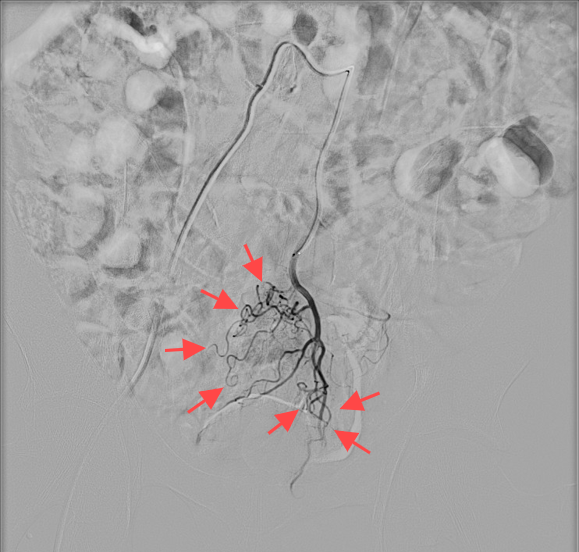

使用金属弹簧圈栓塞后造影显示痔血管基本消失

术后刘大爷便血即刻停止,未出现肠道缺血坏死症状,术后第三天顺利出院。